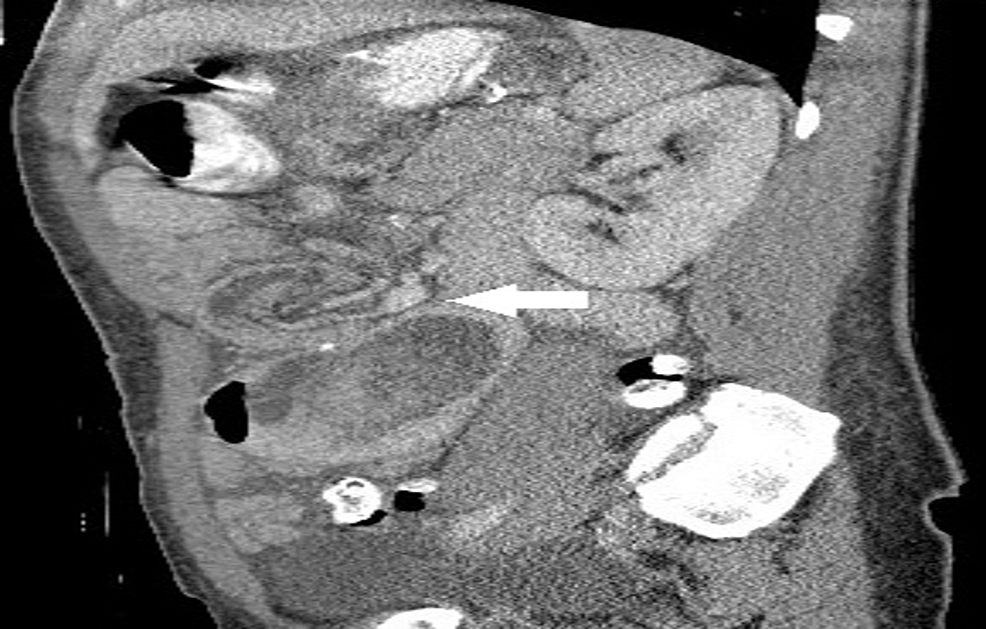

Abdominal/pelvic CT showing a large retrograde jejunogastric Gastric Bypass Intussusception Radiology It could cause abdominal pain and. Intussusception occurs when one segment of the bowel is pulled into itself or a neighboring loop of the bowel by peristalsis. Prompt diagnosis is critical as. It is an important cause of an acute abdomen in. With unclear risk factors and a variable presentation,. Gastric Bypass Intussusception Radiology.